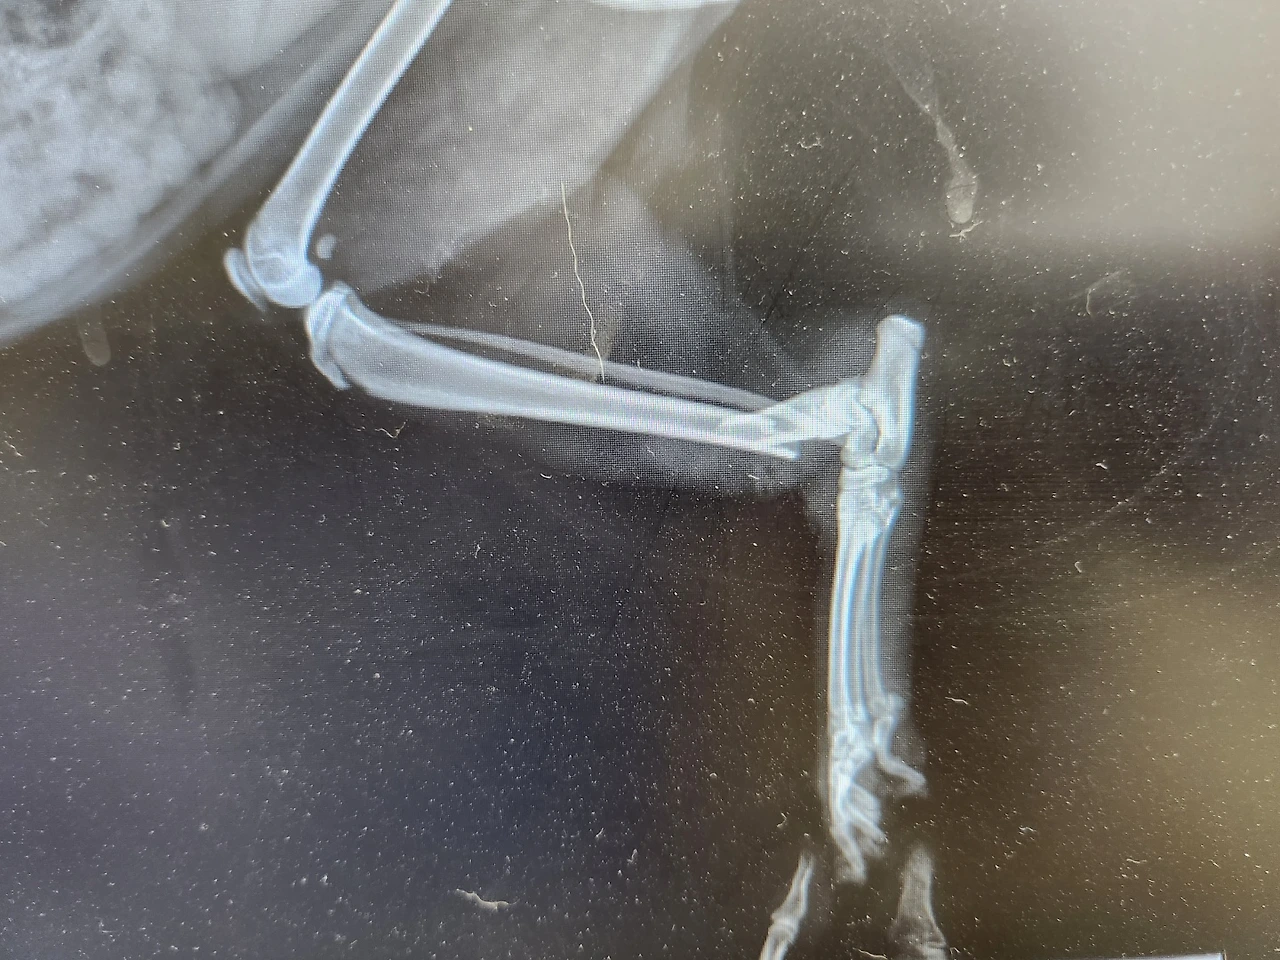

뒷다리가 골절되고 찢어진 상처부위로

감염이 심해서 한달 또는 두달이나

입원치료를 받아야 한다고해요